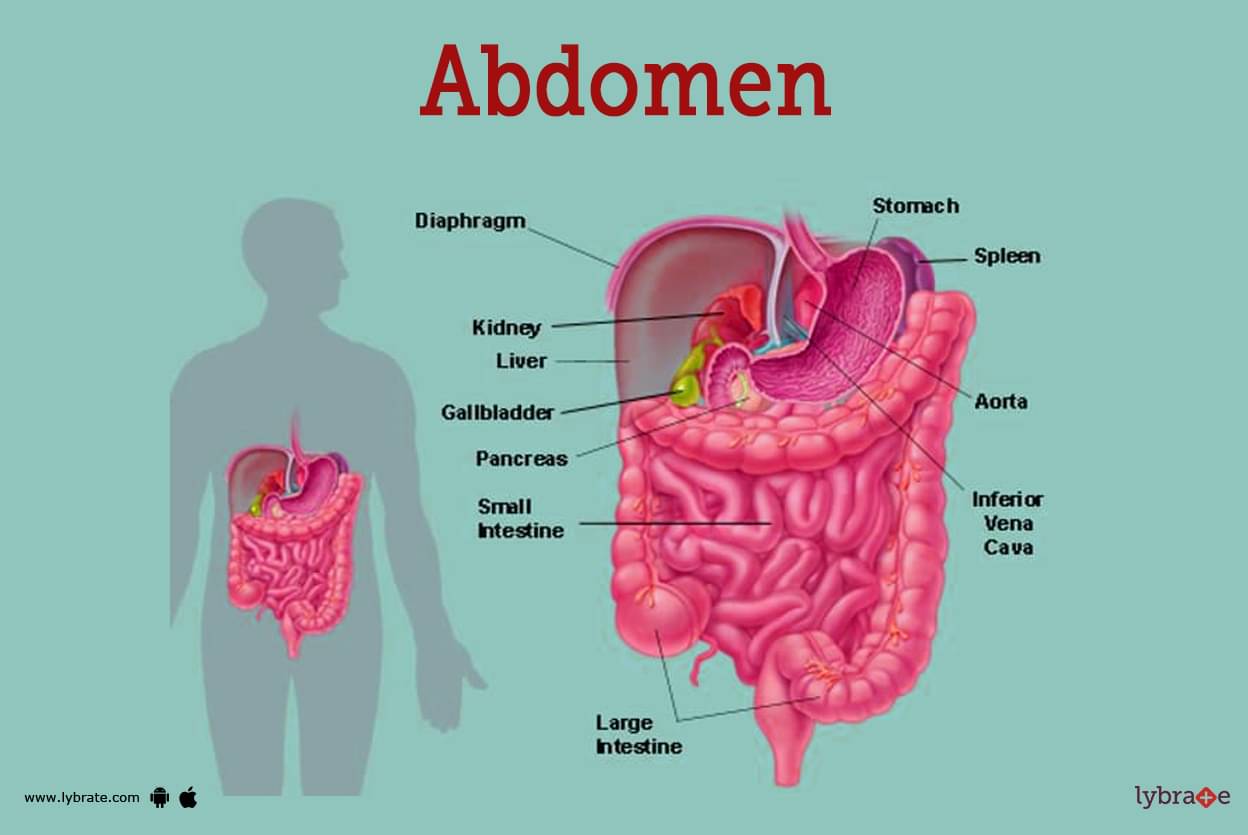

completeanatomy.cnAbdomen (Human Anatomy) - Image, Definition, Function, Diseases And More

completeanatomy.cnAbdomen (Human Anatomy) - Image, Definition, Function, Diseases And More

www.lybrate.com3d Illustration Of The Internal Abdominal Muscles Anatomical Position

www.lybrate.com3d Illustration Of The Internal Abdominal Muscles Anatomical Position